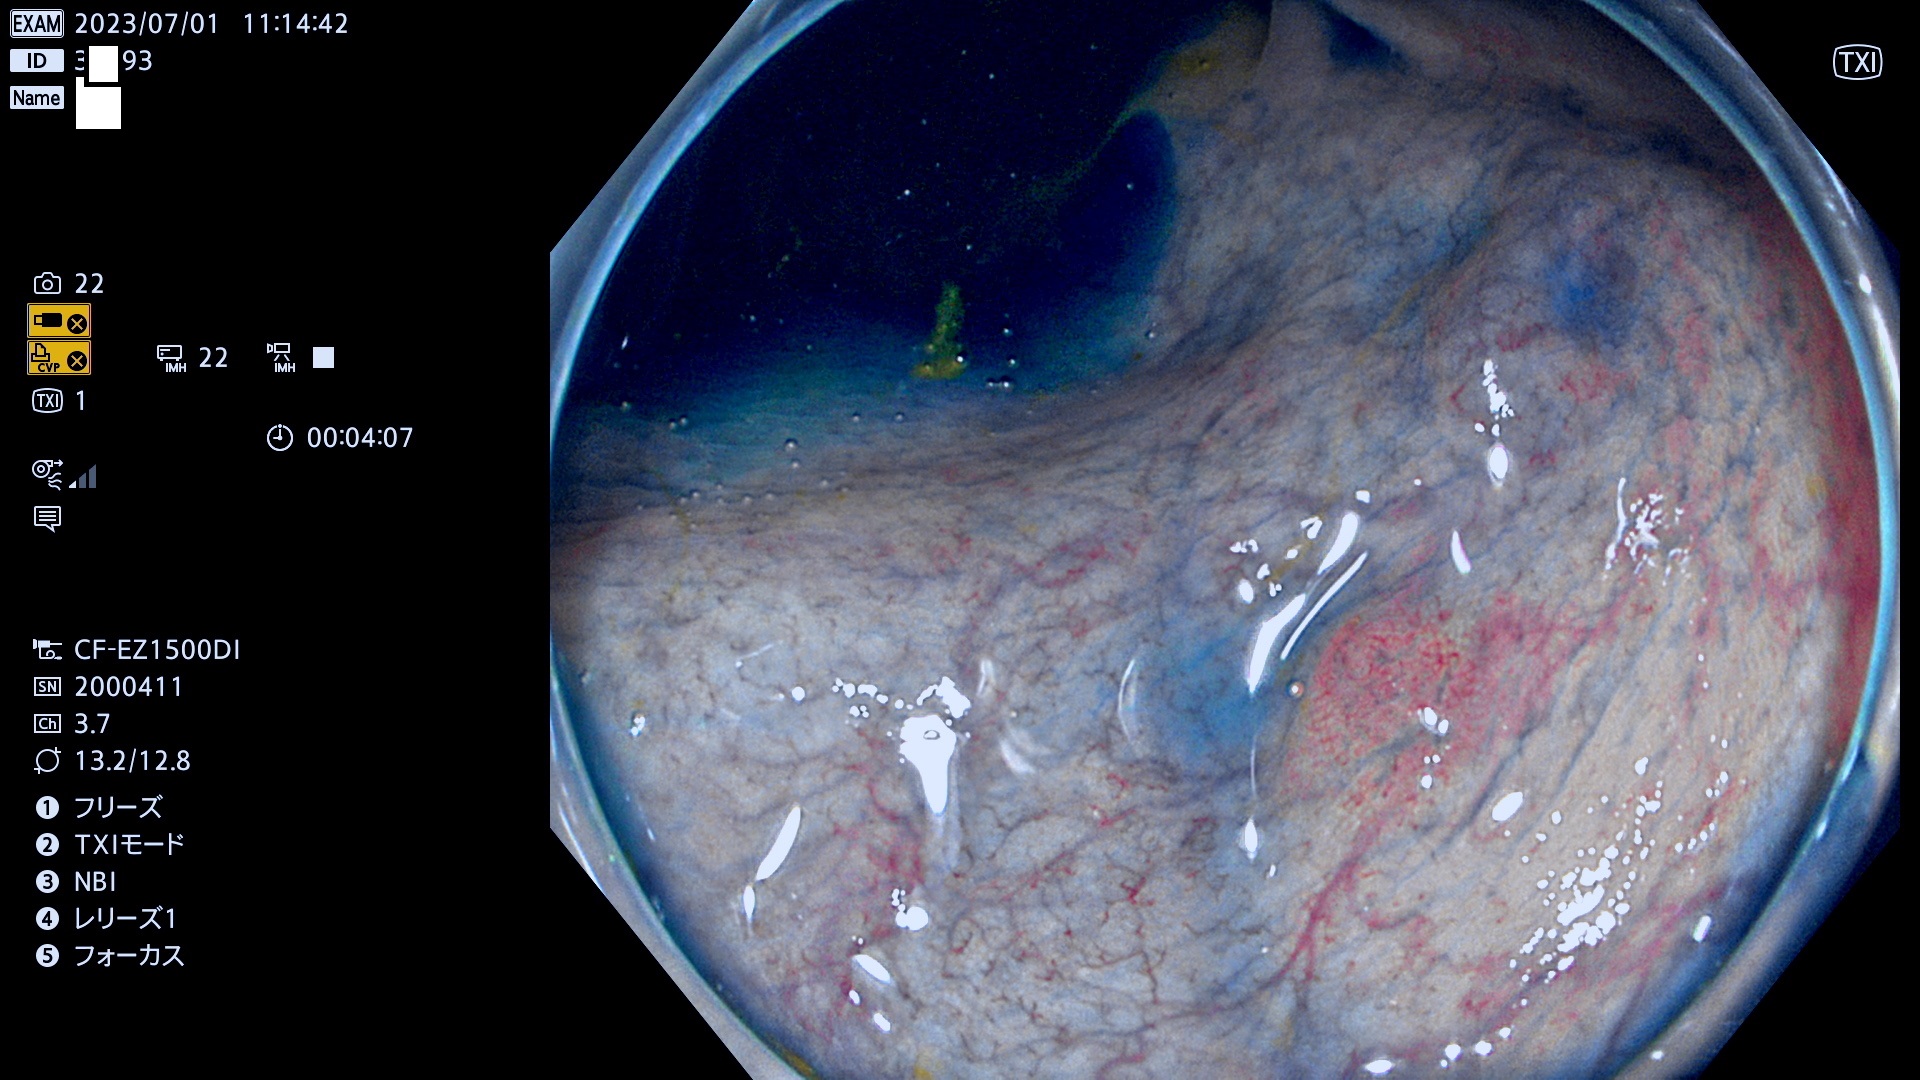

「表面型腫瘍」の中で、完全に平坦な物をUb、陥凹している物をUcと呼びます。平坦隆起型(Ua)よりも、発見が難しく危険な病変です。このタイプの発見率は「腺腫発見率」よりも、遥かに重要な意義があります。

抽出の対象期間 2023年6月29日(木)〜7月2(日)の4日間(48件の検査)8件